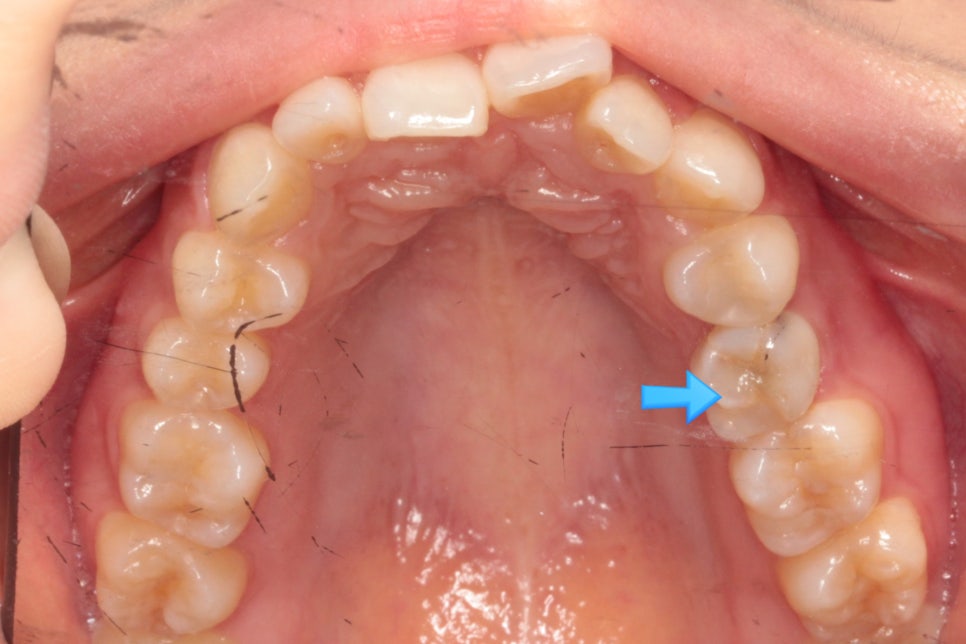

심한 덧니와 과개교합을 보이고 있는 환자분입니다.

그리고 한개 치아의 #선천적결손 이 관찰됩니다.

화살표 부위가 결손치아입니다. 유치가 남아있네요.

임플란트를 안하기 위해 공간을 닫는 옵션과 임플란트를 하는 옵션 두개를 환자분과 상의하였습니다.

환자분은 비교적 치료기간이 짧은 #임플란트 식립 계획을 선택하셨습니다.

임플란트를 위한 공간을 조절하는 과정에서 화살표부위의 교합이 맞지 않게 1set가 끝났습니다.

앞니의 배열도 약간은 아쉬움이 보여 재제작을 하기로 했습니다.